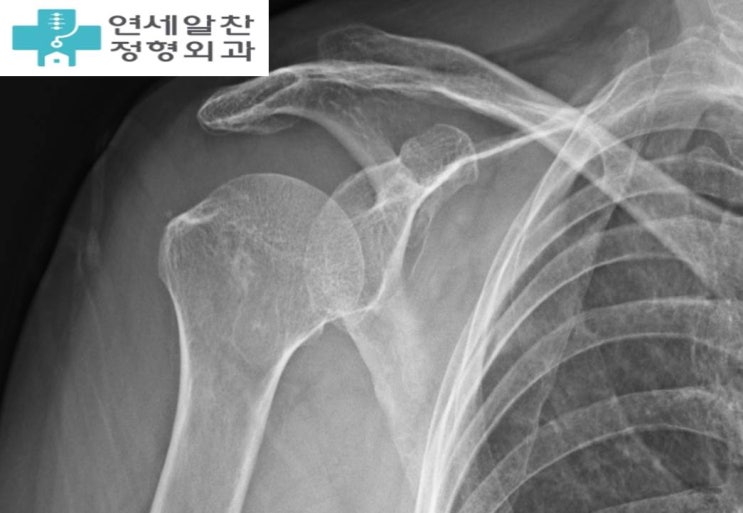

회전근개 재파열, 회전근개 재수술, 상부관절낭재건술

이번 케이스는 회전근개 일차 봉합술이 잘못되어 재파열이 일어난 경우이다. 환자는 10개월전 수술적 치료...